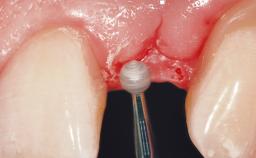

A 30-year-old female patient was referred to the office for the treatment of tooth 11. Her chief concern at the initial visit was to inquire, “Why is my tooth pink?” Upon clinical examination, it was determined that tooth 11 had a previous history of trauma and that the clinical crown had become noticeably pink in color as a result of internal resorption. This diagnosis was confirmed radiographically, indicating a large radiolucency involving the central and distal portions of the clinical crown. It was determined that restoration of this tooth was not possible, and that extraction was indicated. The presence of a mid-line diastema, which the patient wanted to reproduce, directed the treatment plan for tooth replacement utilizing a dental implant.

Bone Augmentation Horizontal|Simultaneous

Augmentation Materials Autogenous chips|Membrane

Placement Protocol Immediate implant placement